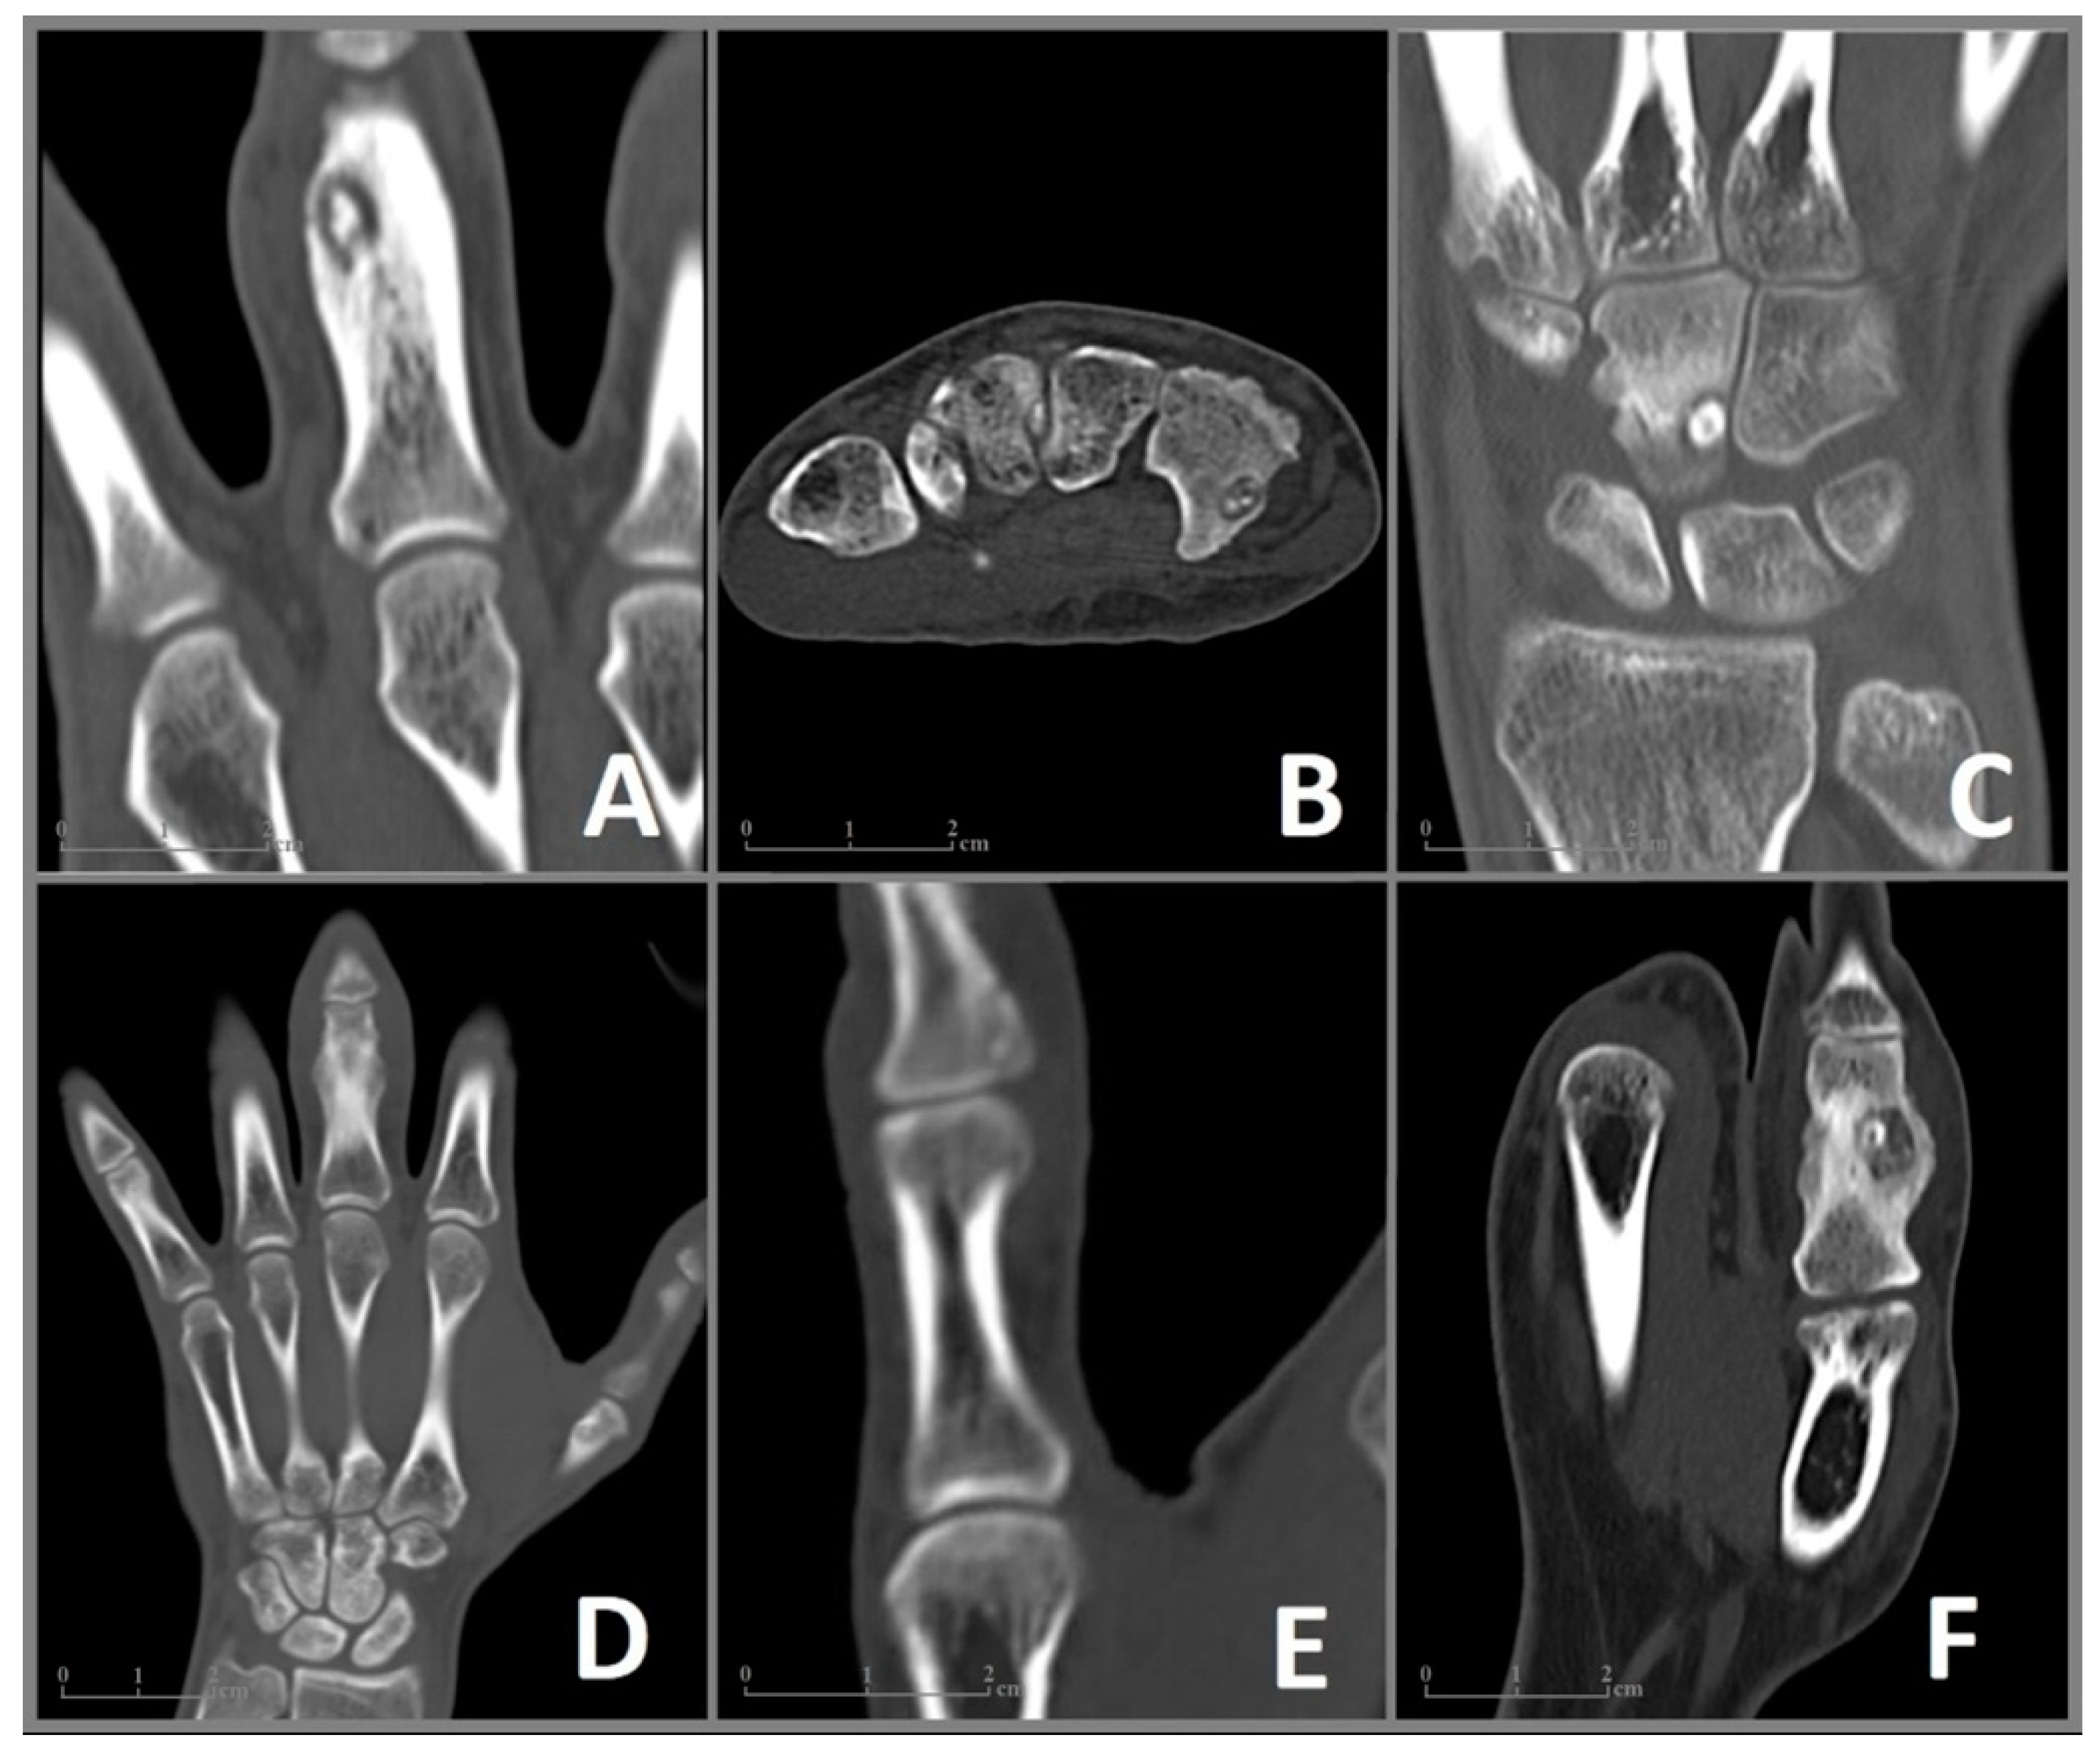

Figure 2.

CT imaging of the included cases 1–6 (A–F) of OO in the bones of the hand. (A) Case 1: Coronal CT image showing a nidus with a diameter of 9 × 6 mm and surrounding sclerosis in the proximal phalanx of the left middle finger. (B) Case 2: Axial CT image of a 6 × 4 mm nidus in the hook of the hamate. (C) Case 3: Coronal CT image revealing a juxta-articular nidus (7 × 5 mm) at the ulnar surface of the capitate. (D) Case 4: Coronal CT image showing enlargement and deformation in the proximal phalanx of the middle finger. The nidus (10 × 7 mm) is difficult to distinguish. (E) Case 5: Coronal CT Image of a 6 mm nidus in the distal phalanx in close proximity to the interphalangeal joint. (F) Case 6: Coronal CT image showing a 9 × 8 mm nidus in the proximal phalanx of the thumb with pronounced sclerosis as well as deformation and enlargement of the affected bone.